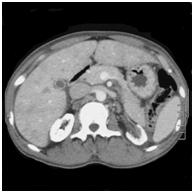

Figure 2 Non contrast enhanced computed tomography of the abdomen of subject 2. Note the bone-identical density of the renal parenchyma due to oxalate deposition.